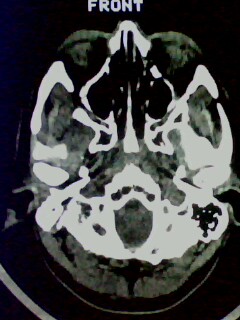

以下是引用随光逐影在2009-5-20 19:22:00的发言:[br]1)考虑左上颌骨近中线区含牙囊肿。2)鼻中隔右突偏曲。3)双侧下鼻甲肥大。